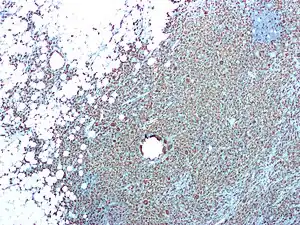

| CD68 immunostaining on this photomicrograph shows macrophages and giant cells in a case of xanthogranulomatous pyelonephritis | |

Xanthogranulomatous pyelonephritis is an unusual form of chronic pyelonephritis characterized by granulomatous abscess formation, severe kidney destruction, and a clinical picture that may resemble renal cell carcinoma and other inflammatory kidney parenchymal diseases. Most affected individuals present with recurrent fevers and urosepsis, anemia, and a painful kidney mass. Other common manifestations include kidney stones and loss of function of the affected kidney. Bacterial cultures of kidney tissue are almost always positive.[25] Microscopically, there are granulomas and lipid-laden macrophages (hence the term xantho-, which means yellow in ancient Greek). It is found in roughly 20% of specimens from surgically managed cases of pyelonephritis.[10]